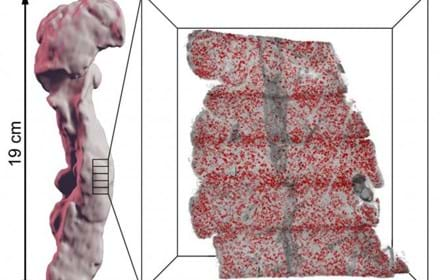

Fotsår vid diabetes kan leda till amputationer

Diabetespatienter amputerar dagligen